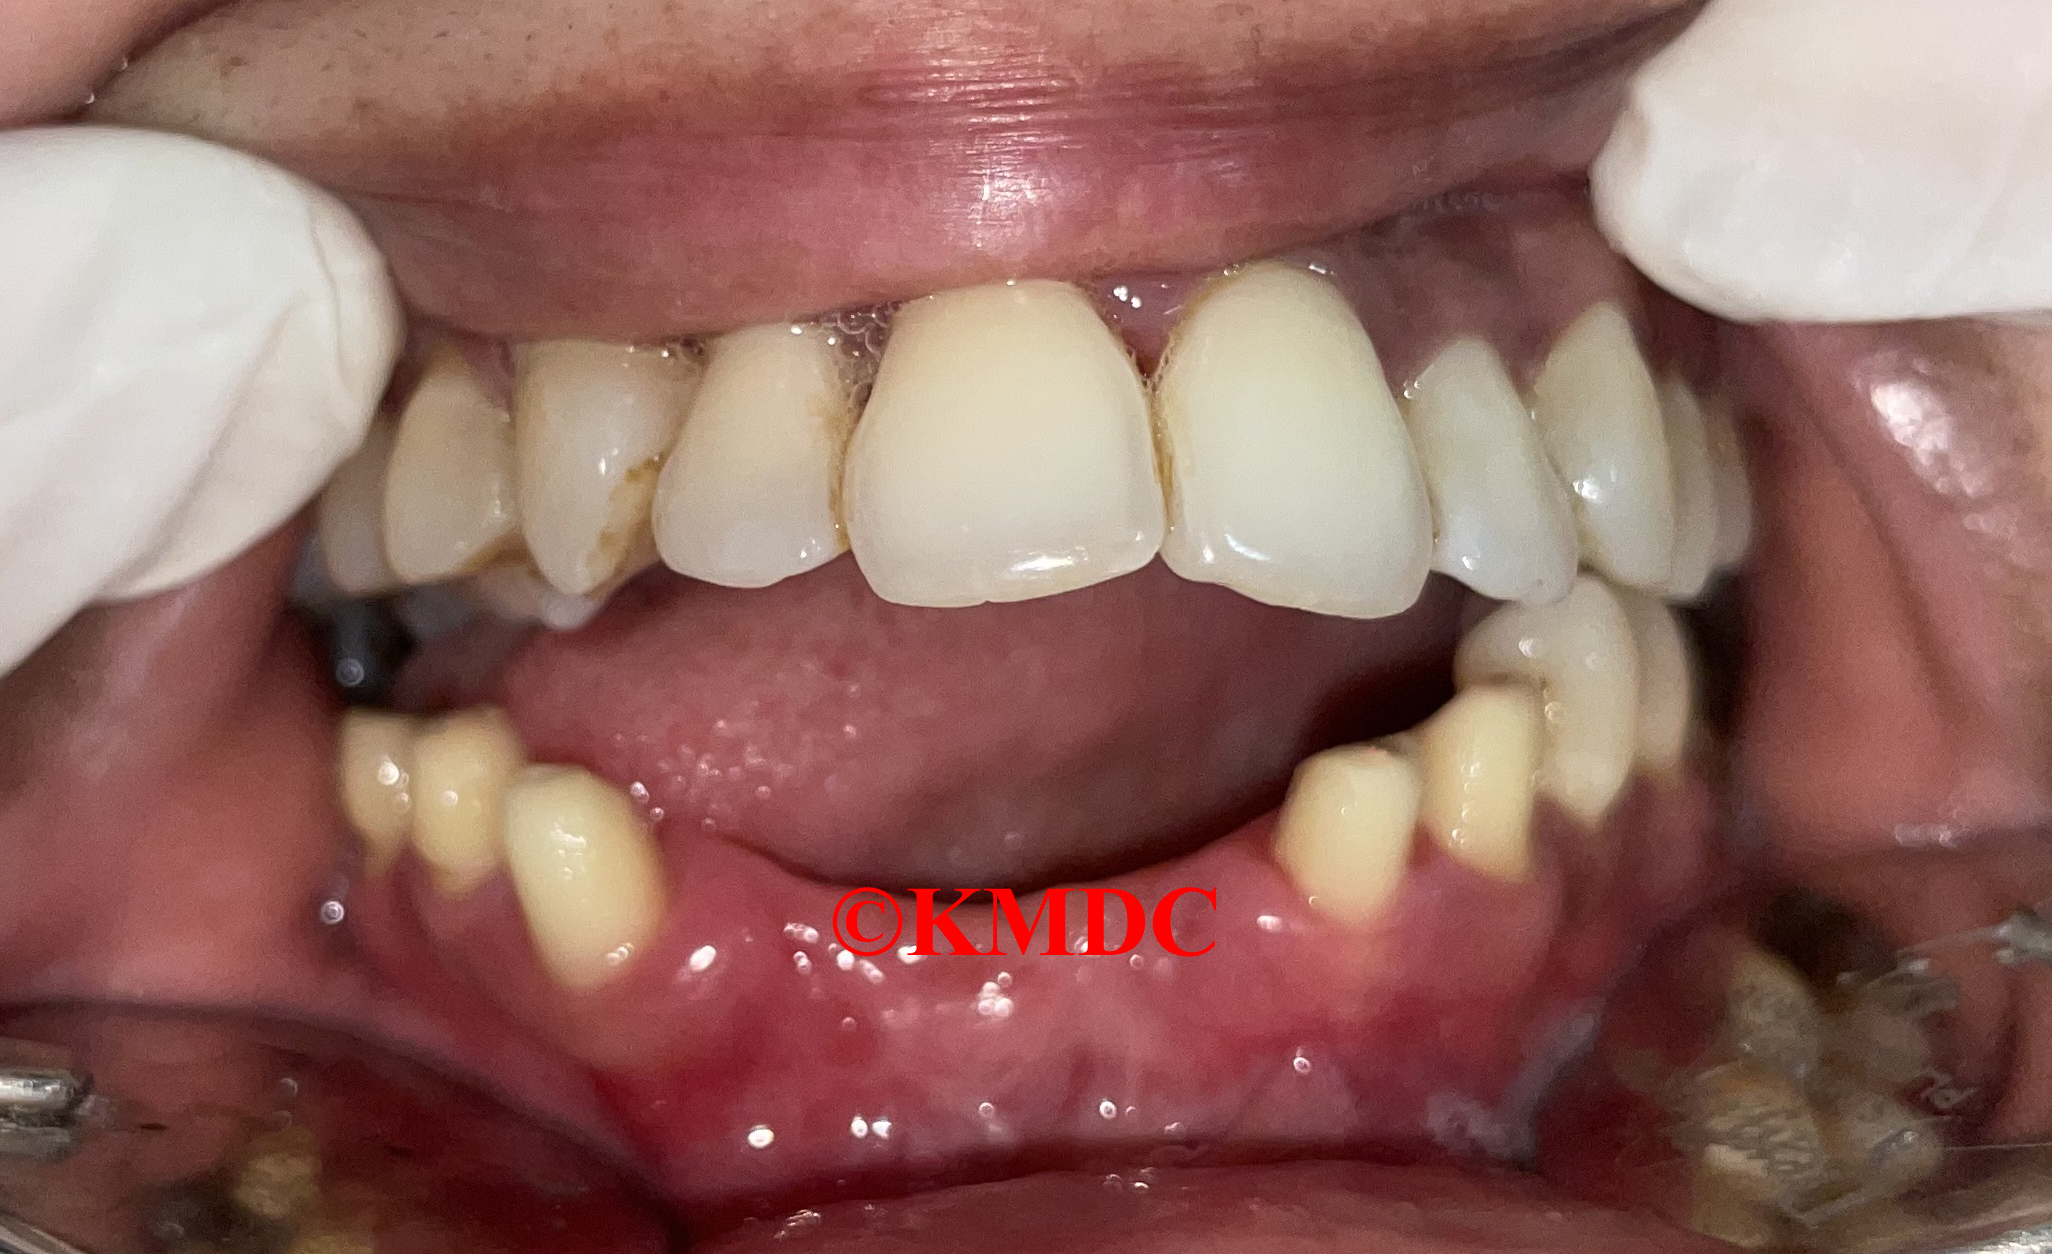

Clinical Gallery